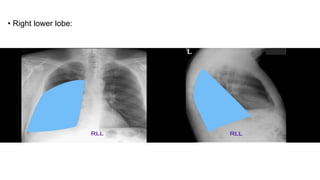

• Right lower lobe:

Lung • There are3 lobes in right lung and 2 in left. Right lung • Upper lobe • Middle lobe • Lower lobe. Left lung : also contains the lingula,part of the upper lobe. • Upper lobe; this contains the lingula • Lower lobe.